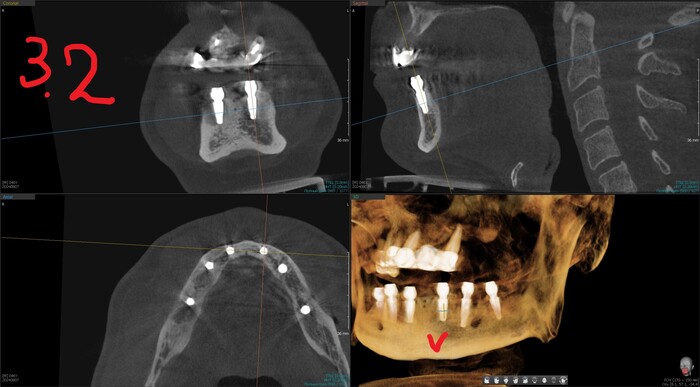

Результат такой - торки получены эталонные везде, кроме двух крайних имплантатов слева (3.4 и 3.6). Но не страшно, сверху зубов-антогонистов нет, нагрузки на протез не будет серьёзной. Да и "всё на 6" прощает подобное.

Имплантаты установлены и пациент отправляется на КЛКТ. Каждый раз очень радуется имплантолог, что аппарат находится в клинике. Я тоже рада)

Имплантолог видит, сколько мм можно докрутить безопасно для структур челюсти (нервов, сосудов). Делает дело.